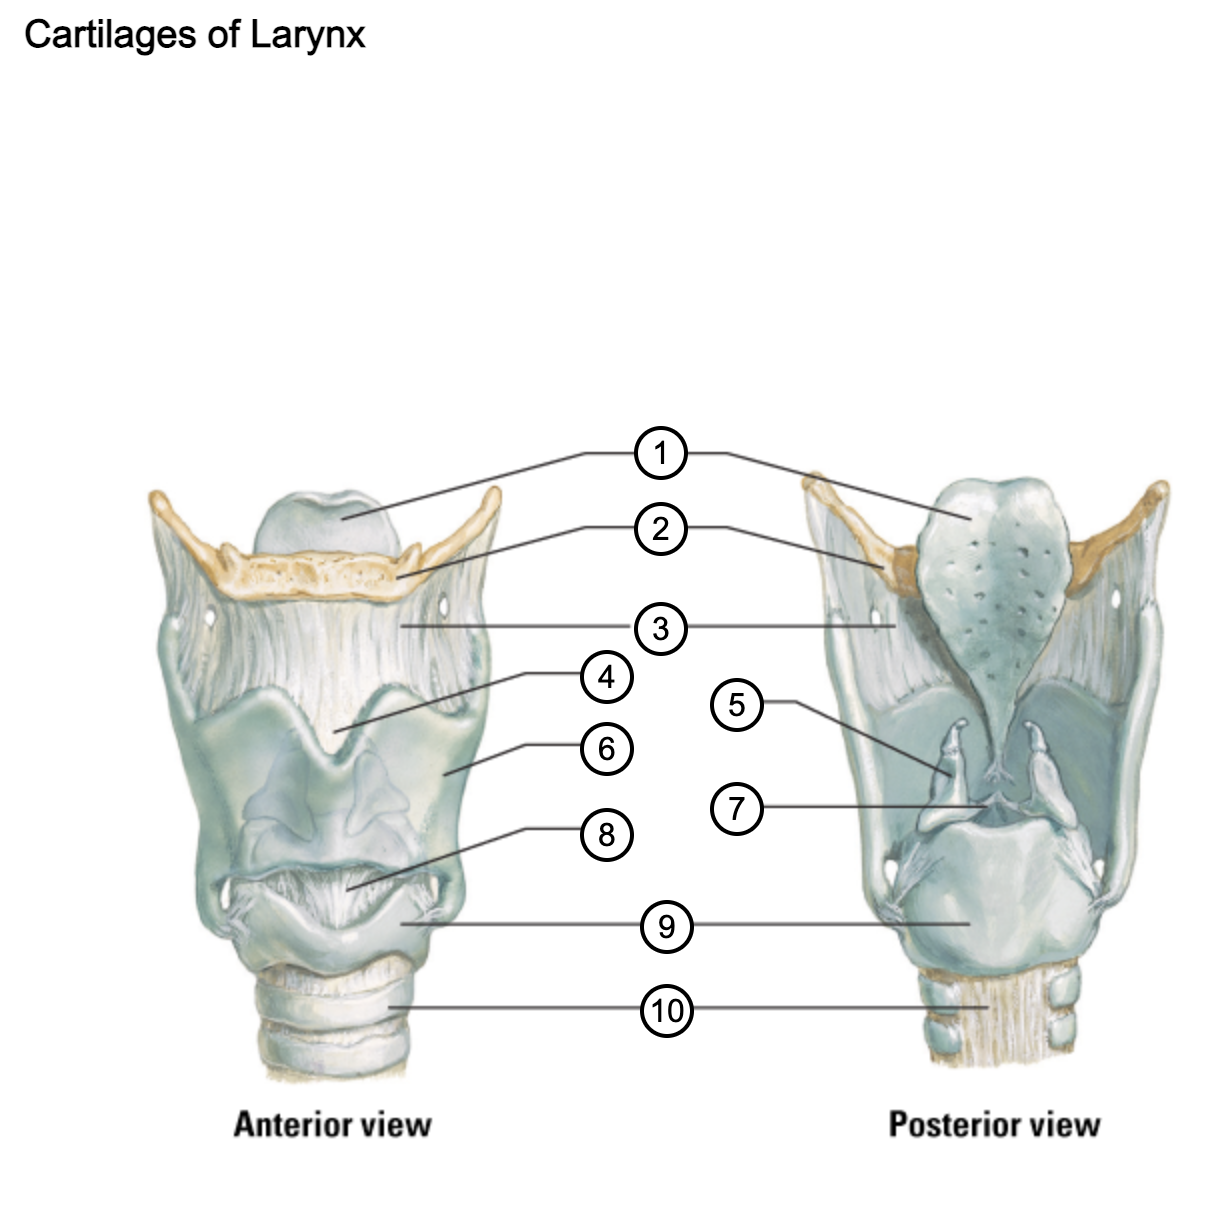

1

epiglottis

2

hyoid bone

3

thyrohyoid membrane

4

superior thyroid notch

5

arytenoid cartilage

6

lamina of thyroid cartilage

7

vocal ligament

8

median cricothyroid ligament

9

cricoid cartilage

10

trachea